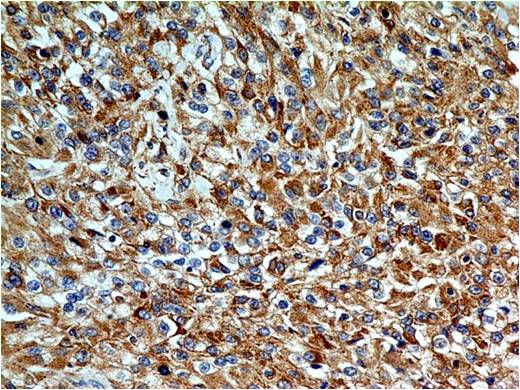

| Application: | FACS, IF, WB, IHC |

Description: TLR2 (Toll-Like Receptors 2) is a member of the TLR (Toll-like receptor) family that plays a fundamental role in pathogen recognition and activation of innate immunity. TLR2 forms heterodimers with TLR1 and TLR6, which is the initial step in a cascade of events leading to significant innate immune responses, development of adaptive immunity to pathogens and protection from immune sequelae related to infection with these pathogens. TLR2 also interacts with a large number of non-TLR molecules, allowing for recognition of a great number and variety of PAMPs (pathogen-associated molecular patterns). TLR2 expression has been detected in immune cells, endothelial, and epithelial cells.

Western blot analysis: 2-4 µg/ml, FACS analysis: 0.5 µg/10^6 cells, Immunohistochemical analysis: 5 µg/ml